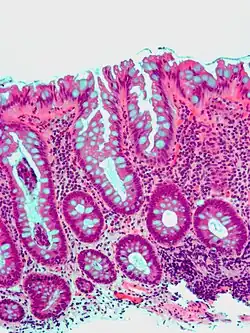

Microvesicular hyperplastic polyp. H&E stain. -

Traditional serrated adenoma. H&E stain. -

Gross appearance of a colectomy specimen containing two colorectal polyps and one invasive colorectal carcinoma -

Micrograph of a tubular adenoma, the most common type of dysplastic polyp in the colon -

-

Micrograph of a tubular adenoma – dysplastic epithelium (dark purple) on left of image; normal epithelium (blue) on right. H&E stain. -